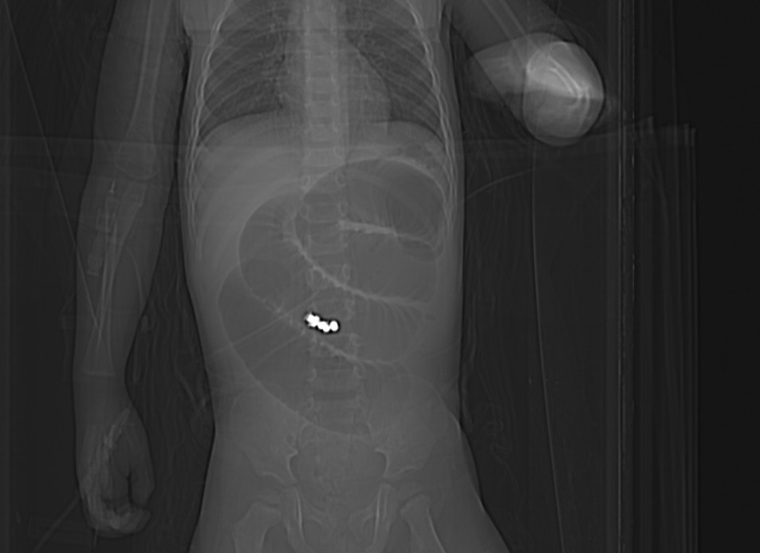

▲X光照片顯示,男童吞下的巴克球在腸內沾黏。(圖/童綜合醫院提供)

【NOW健康 葉立斌/台北報導】有位1歲7個月的王姓男嬰,因為持續3天出現嘔吐症狀,且逐漸不太願意吃東西,家人帶至童綜合醫院急診室就醫,醫師透過X光檢查發現小腸處有異物;緊急會診小兒外科郭敏勇主任與一般外科張孟浩醫師,再進行斷層掃瞄檢查後,研判男嬰小腸內不只1顆的圓形異物,並且已經造成腸阻塞,緊急安排進行手術。

童綜合醫院小兒外科郭敏勇主任進行阻塞部位的小腸切除手術,並將異物取出,才發現原來是小男嬰吞進了8顆巴克球導致,因為巴克球的超強磁性造成小腸的空腸與迴腸吸附在一起,並且在腸道間形成廔管,還好沒有造成腸液外漏或腹膜炎等嚴重情況。手術順利恢復良好,住院一周即返家休養。